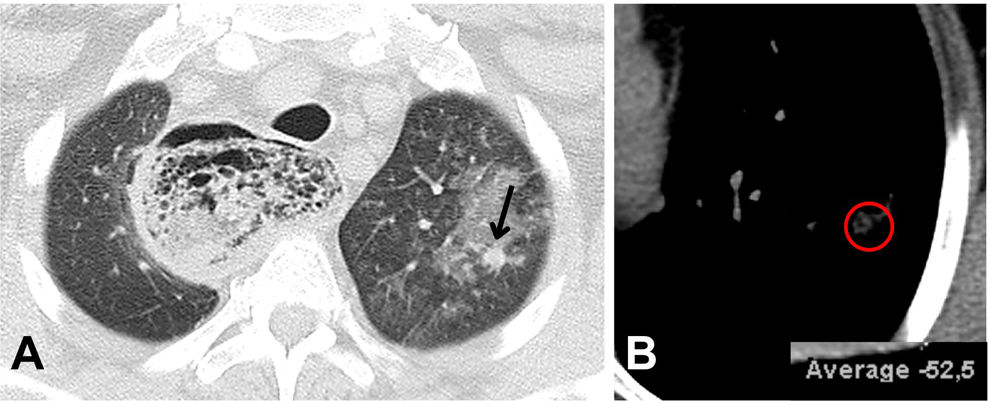

Neumonía lipoidea: a propósito de 2 casos

Two cases of lipoid pneumonia